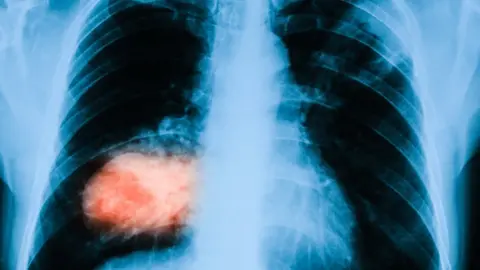

ThinkstockA cancer charity says it is to fund £8.3m of research which was delayed by the first wave of coronavirus.